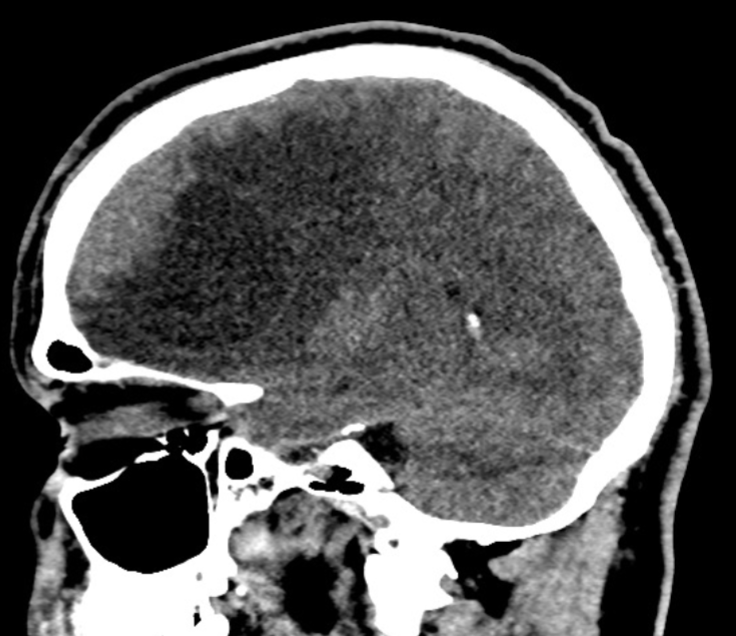

Name the pathology

MCA infarct (necrosis)